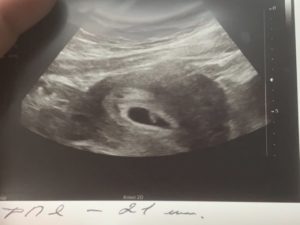

При обследовании может быть назначено УЗИ на 6 неделе беременности. На таком сроке УЗИ позволяет определить наличие плода в матке, то есть, исключить внематочную беременность. Можно увидеть, сколько плодных мешочков начали свое развитие в матке, то есть, выявит многоплодную беременность.

На таком сроке плод мало напоминает ребенка, эмбрион выглядит, как зернышко фасоли, да и его размер напоминает зернышко. Но зато при проведении УЗИ можно будет увидеть сердцебиение плода.

На 6 неделе необходимо сделать первое узи – вы сможете услышать стук сердца малыша.